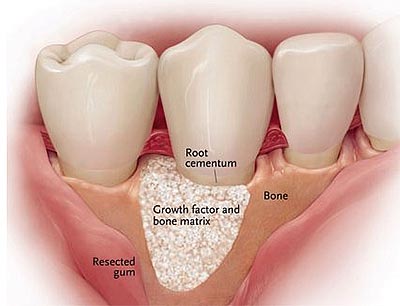

Regenerative Procedures

In cases of bone or tissue loss, regenerative techniques may be used to encourage the body to rebuild lost structures and support long-term stability.